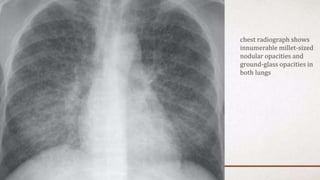

F-Lung Fields • Normally,there are visible markings throughout the lungs due to the pulmonary arteries and veins, continuing all the way to the chest wall. • Both lungs should be scanned, starting at the apices and working downward, comparing the left and right lung fields at the same level.